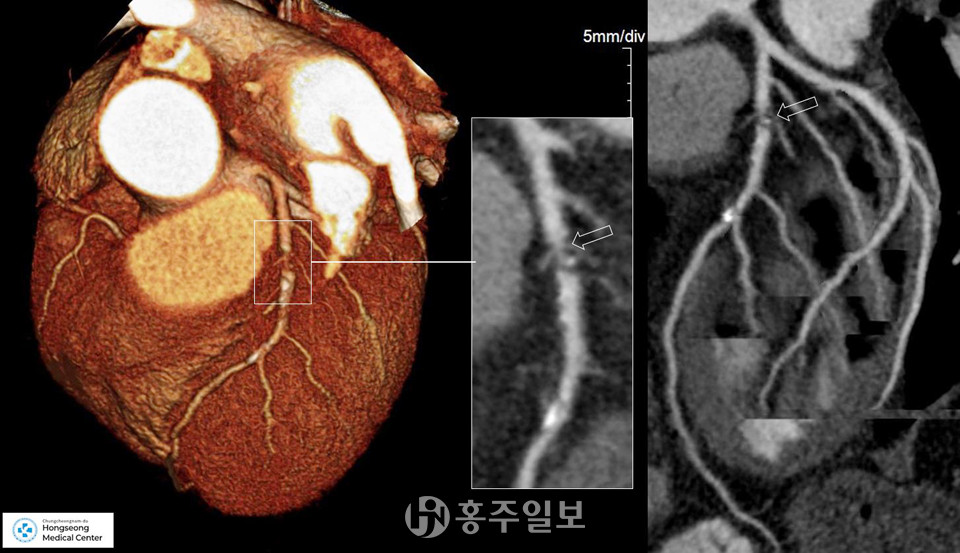

경희대병원 심혈관센터장과 한국심초음파 학회장을 역임한 심장초음파 분야의 국내 권위자 김권삼 과장과 순천향대병원 심장CT 전문 교수 출신 이헌 영상의학과 과장이 홍성의료원에 새롭게 합류해 검사의 정확성과 신뢰성을 한층 더 높이고 있다.

특히 대학병원급의 최신 CT는 심장질환 진단의 정밀도를 크게 높여 관상동맥질환을 조기에 진단할 수 있는 중요한 도구로 자리 잡았으며, 지역 내에서 심혈관질환의 조기 발견 사례가 증가하고 있다.